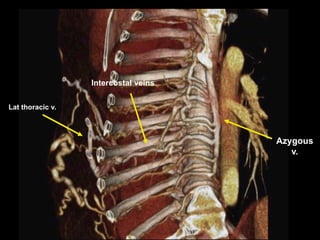

Lat thoracic v.

Intercostal veins

Azygous

v.